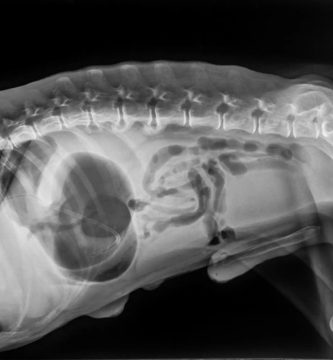

Bloat